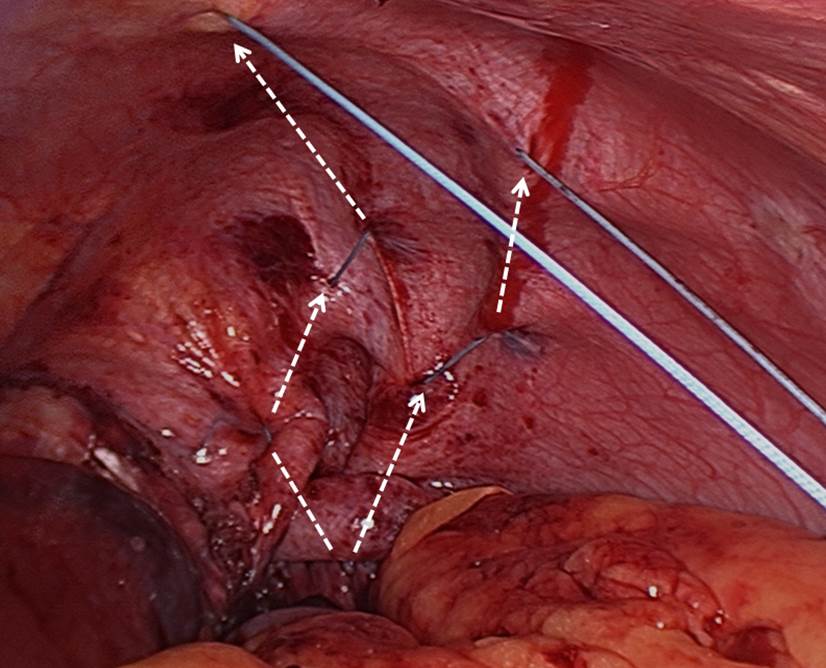

- Stitching: The authors use pledgeted U-stitches (#2 non-absorbable, braided suture, 31 mm curved needle). The first stitch is placed centrally and as far posteriorly as possible (Figure 3A). Traction on the first stitch facilitates exposure for two or three subsequent deeper stitches to plicate the posterior portion of the hemidiaphragm in an anteroposterior direction (Figures 3B, 3C, 3D). To plicate the anterior portion of the hemidiaphragm, two to three weaving stitches are placed (Figure 4). The diaphragm must be taut at the end of the procedure. Closure of the initial perforation at the dome occurs with the plication.

Figure 3: Technique for suture placement and antero-

posterior plication.